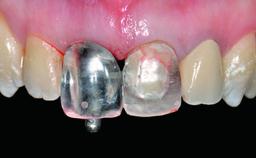

Immediate Loading of Six Implants in the Maxilla and Final Restoration with a Full-Arch CAD/CAM Zirconia FDP

A 63-year-old male patient was referred for a consultation and treatment of partial edentulism in the maxilla. The patient presented with residual anterior teeth and declined a partial removable prosthesis. He reported that the maxillary posterior teeth had been extracted due to mobility and periodontal disease two months before the consultation. The patient’s chief complaint was that his residual maxillary teeth were mobile and that he was unable to chew. The patient’s desire was a stable and comfortable fixed maxillary rehabilitation. The patient was a light smoker (fewer than 10 cigarettes/ day), and his medical history was without significant findings. He was not on any regular medication at the time of consultation. The extraoral examination revealed a normal physiognomy with a correct distribution of the facial thirds. The patient presented a low lip line, and the transition line between teeth and soft tissues was not exposed during a forced smile.

Loading Protocol Immediate

Retention Cemented, with prosthesis margin < 3mm submucosal Cemented, with prosthesis margin < 3mm submucosal

Provisional Implant-Supported Prosthesis Prosthodontic margin < 3 mm apical to mucosal crest Prosthodontic margin < 3 mm apical to mucosal crest